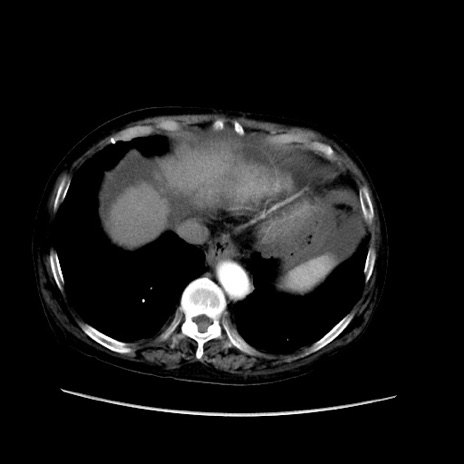

冠状断像